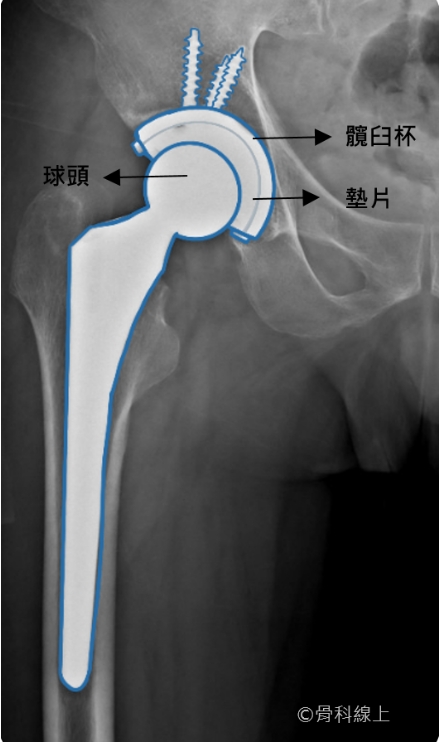

人工髖關節脫臼,指的是原本位在髖臼杯(cup)裡面的球頭(head)脫離了原本所在的位置,此時人工髖關節完全失去載重、活動的功能,病患通常完全無法行走、甚至輕微動作就感到劇烈疼痛。

正常的 X 光【球頭仍在髖臼杯中】

而雙動式人工髖關節(dual mobility total hip arthroplasty)的設計,簡單來說,是把聚乙烯墊片做成另外一個球頭(大頭, shell),套在原本的髖關節球頭(小頭, head)上,所以小頭與大頭間可以活動,大頭與髖臼杯間也可以活動,也就是所謂 “雙動”(dual mobility)的名稱由來。正因為大頭的直徑大小遠超過一般人工關節球頭,脫臼的機會就可以大幅下降。